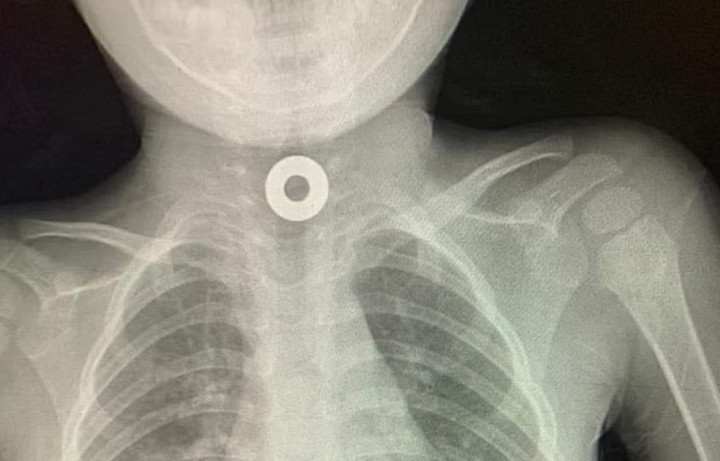

طائف میں ڈاکٹروں نے بچے کے حلق سے دھاتی نٹ نکال لیا

طائف: بچے کے حلق میں پھنسا سکہ نکال لیا گیا